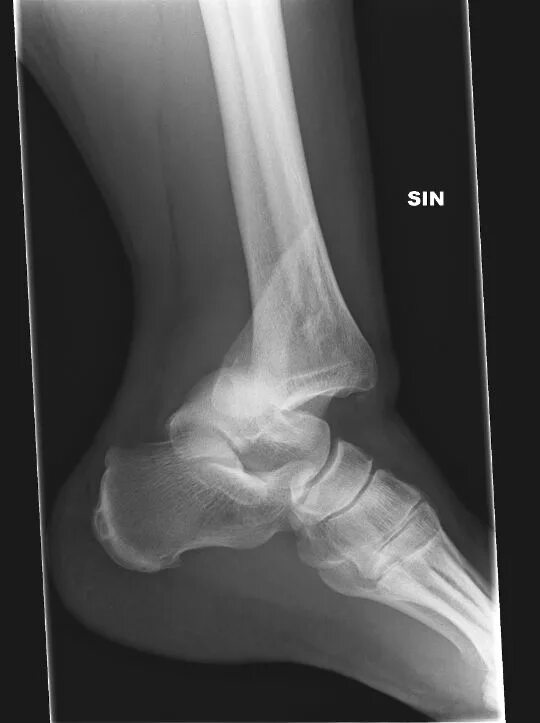

Вывих со смещением